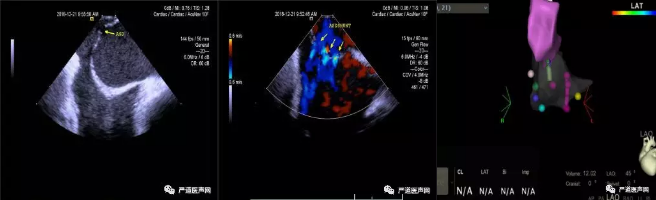

3D-ICE检查结果

12月21日晨07:30,张玉顺教授团队早早来到介入手术室,大家提前准备好各种抢救设备,做好每个环节的准备工作,08:00手术正式开始。台上所有手术人员忙而有序,紧密配合;张教授聚精会神,紧盯屏幕,用娴熟的技术操作着CartoSound 3D-ICE导管,精确地显示了房间隔膨出瘤的大小、幅度及瘤壁上的筛孔,并应用强生公司CARTO 3三维电生理导航系统结合CartoSound 3D-ICE导管精准还原6处缺损的三维空间位置;在3D-ICE指导下,反复调整导丝、导管的走向,如同在梅花针孔中央穿针引线,精准过房间隔膨出瘤中心位置的小缺损后,放置一枚40mm特殊Amplazer筛孔ASD封堵器,将瘤壁上所有的筛孔完美封堵,手术全程历时仅半小时左右,赢得了手术台下医务工作者的阵阵掌声,台上的患者也不由叫好,发自肺腑地对张教授说:“太感谢您了,张教授!”